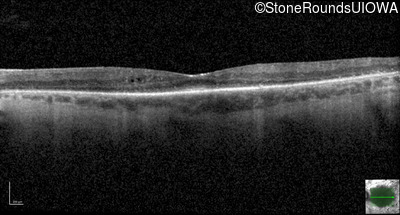

Optical Coherence Tomography - Right - 20/40 +2

Exemplar / OCT Stack

OCT Stack